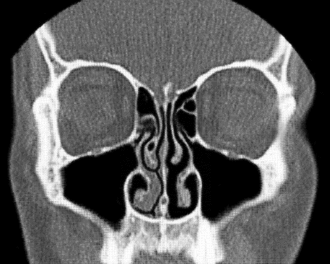

CT-Schnittbild aus koronaler Schichtung des Gesichtsschädels (mit Nasennebenhöhlen, Nasenseptum, Nasenmuscheln)

In der Medizin wird eine Frontalebene des Kopfes auch als Coronalebene oder Koronalebene bezeichnet. Insbesondere bei der tomographischen Bildgebung spielen Frontalschnitte – meist Koronalschnitte oder Koronarschnitte genannt – als parallel zu einer Frontalebene aufgenommene oder nachträglich in dieser Orientierung rekonstruierte Bilddaten eine wichtige Rolle. Aus der tomographischen Untersuchung in dieser Ebene ergeben sich die koronalen Schichtungen, die den Körper eines untersuchten Patienten so darstellen, dass sich von vorne nach hinten aufeinanderfolgende Schichten betrachten lassen.[1]